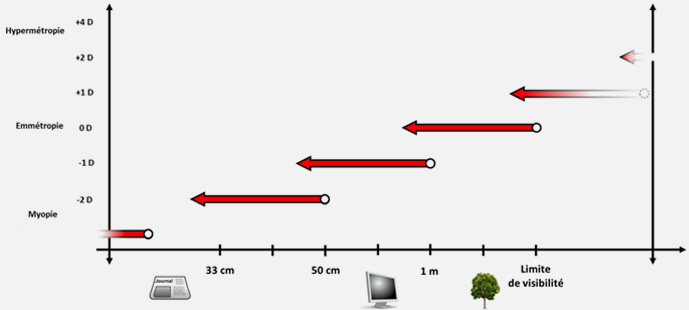

La presbytie est un trouble de la vision lié à l'âge, correspondant à la diminution progressive de la capacité d'accommodation de l'oeil. Elle est généralement associée à une difficulté à voir de près.

L'accommodation est le mécanisme permettant à l'oeil de voir à plusieurs distances. Ce mécanisme repose sur la capacité du cristallin à se déformer et à ajuster sa puissance.

En effet, si l'oeil était statique, l'emmétrope (c'est-à-dire une personne sans défaut de vision) ne pourrait voir net que de loin car les images des objets proches se formeraient en arrière de la rétine et apparaîtraient donc floues.

En augmentant sa puissance, le cristallin permet de corriger cela en ramenant l'image de l'objet sur la rétine.